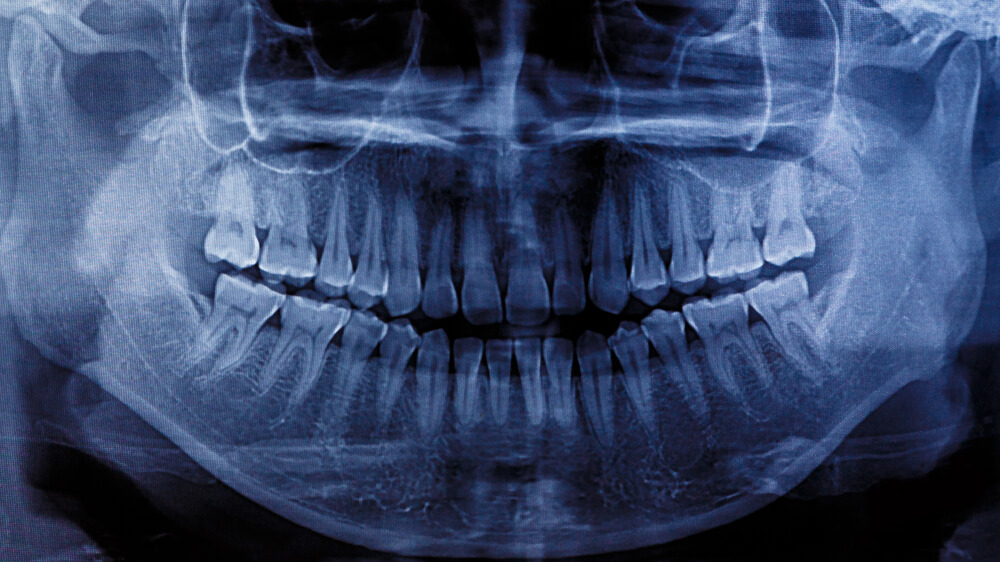

I pour my savings into my mouth and they keep taking teeth out. Insurance deems them luxury bones, decided how much is worth spending on them, never mind the cost to my health. Never mind what I must forgo to make up the difference, and how I and so many others must just accustom themselves to the cheap pull and the empty space. Learning to chew on just one side, to swap tips on saltwater and clove oil. To tongue the divots like a worry stone.

The teeth they offer as replacement cost the same as a used car. The same as a years’ worth of rent. Well, not anymore. Let’s say half a years’ worth of rent. In an old house with quirks. With 3 housemates and a heater that never goes above 60 degrees. Counting our change for bus fare. Counting ourselves lucky. To have a job to bus to. To have a home to bus back to. Lucky to have food to chew on one side of our mouth.